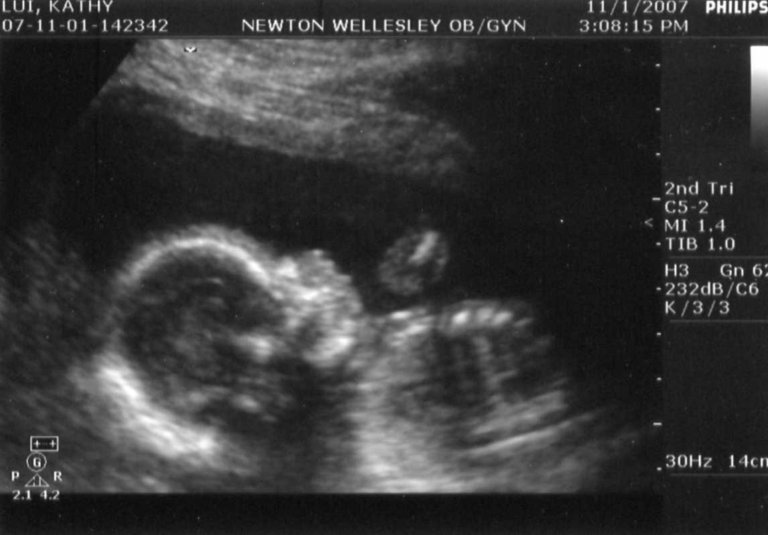

Jon thinks this next one was her Halloween costume - a goblin!